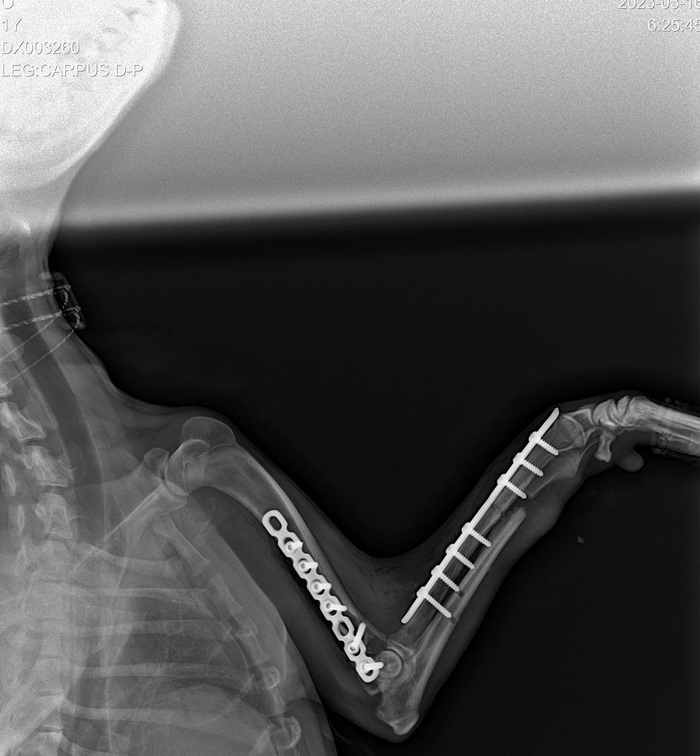

О нашей подопечной Боне мы уже писали. Это она — переломанная в автотравме у Боровского монастыря собака. Лечение продолжается, и суммы на него космические.

Бона попала под трактор несколько дней тому назад. Результат — скальпированная рана хвоста, множественные переломы опорно-двигательного аппарата. Все проблемы решаются постепенно: несколько дней назад была первая операция, на которой собрали переднюю лапу. Вчера ночью была проведена вторая операция, в ходе которой по кусочкам собирали таз и удалили часть хвоста.

Выше - вторая, вчерашняя операция. Ниже - первая, которая была пару дней назад (на нее ругается баянометр - снимок уже был в посте о Боне раньше, но не приложить его и сюда было бы неправильно).

Бона молодец. Пока на обезболивающих, и это неизбежно. Даже после всего произошедшего доверчиво тянется к людям, радуется поглаживаниям, наивно хлопает красивыми глазками. Уверены: пройдет положенное на восстановление время и Бона поправится. Чтобы искать самых Своих людей.